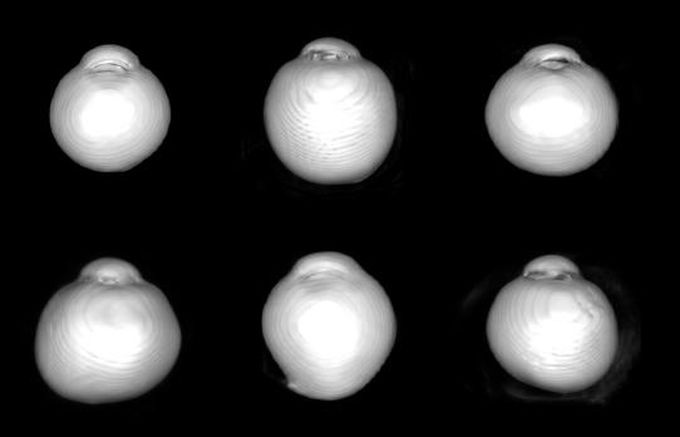

[µ¥Àϸ®¸Þµð ¹Ú´ëÁø ±âÀÚ] º¸¶ó¸Åº´¿ø ¾È°ú ±è¼®È¯ ±³¼öÆÀÀÇ ¾È±¸ ÇüÅ¿¡ µû¸¥ ½Ã½Å°æ ÇüÅ º¯È­ ¿¬±¸°¡ ÃÖ±Ù ±¹Á¦ÇмúÁö ‘Ophthalmology’¿¡ °ÔÀçµÆ´Ù.

±è¼®È¯ ±³¼öÆÀÀº 3D-MRI ºÐ¼®À» ÅëÇØ ¾È±¸ÀÇ 3Â÷¿øÀû ÇüŰ¡ ½Ã½Å°æ ÇüÅÂ¿Í ¹ÐÁ¢ÇÑ °ü°è¸¦ °®´Â´Ù´Â »ç½ÇÀ» ¼¼°è ÃÖÃÊ·Î ÀÔÁõÇØ³Â´Ù.

½Ã½Å°æÀº ½ÃÀÚ±ØÀ» ¹Þ¾ÆµéÀÎ ¸Á¸·½Å°æÀý¼¼Æ÷°¡ ³ú¿Í ¿¬Á¢Çϱâ À§ÇØ ¾È±¸¸¦ ºüÁ®³ª°¡´Â ÃâÀÔ¹® ¿ªÇÒÀ» Çϴµ¥, ÀÌ´Â ¸Á¸·Ãþ°ú °ø¸·Ãþ Á¤·Ä »óÅ¿¡ µû¶ó ´Ù¾çÇÑ ¸ð¾çÀ» °®´Â´Ù.

¿¬±¸ÁøÀº ¾È±¸°¡ ÆØÃ¢ÇØµµ ¸Á¸·Ãþ¿¡¼­´Â ¾È±¸ ÇØ»óµµ¸¦ À¯ÁöÇϱâ À§ÇØ È²¹ÝºÎÀÇ ¼¼Æ÷ ¹Ðµµ¸¦ º¸Á¸ÇÏ°í ¾È±¸ Àûµµ ¹æÇâ¿¡¼­ ÁÖµÈ ÆØÃ¢ÀÌ ÀÌ·ïÁö´Â °ÍÀ¸·Î ÆÇ´ÜÇß´Ù.

¹Ý¸é °ø¸·¿¡¼­´Â ±×·± Â÷À̸¦ ±â´ëÇÒ ¼ö ¾ø±â ¶§¹®¿¡ ¸Á¸· Ãþ°ú °ø¸· ÃþÀÇ Á¤·Ä »óÅ º¯È­°¡ »ý±â°í ÀÌ·Î ÀÎÇØ ½Ã½Å°æ ¸ð¾ç º¯È­°¡ ¾ß±âµÈ´Ù´Â »ç½ÇÀ» ±Ô¸íÇß´Ù.

Ư¼öÇÑ ½Ã½Å°æ º¯ÇüÀº ³ì³»Àå ¹ß»ý°ú ¹ÐÁ¢ÇÑ °ü°è°¡ Àֱ⠶§¹®¿¡ ÀÓ»óÀûÀ¸·Î ¾ÆÁÖ Áß¿äÇÏ´Ù.

±³½ÅÀúÀÚÀÎ ±è¼®È¯ ±³¼ö´Â “À̹ø ¿¬±¸´Â ½Ã½Å°æ °Ë»ç¸¦ ÅëÇØ °ú°Å ¾È±¸ ¼ºÀå °úÁ¤ Áß¿¡ ÀÖ¾ú´ø º¯È­¸¦ ÃßÃøÇÒ ¼ö ÀÖ´Ù´Â »ç½ÇÀ» È®ÀÎÇÑ °Í¿¡ Å« ÀÇÀǰ¡ ÀÖ´Ù”°í ¸»Çß´Ù.

ÀÌ¾î “°ø¸·Ãþ¿¡´Â ³ì³»Àå ¹ßº´¿¡ ÁÖµÈ ¿ªÇÒÀ» ÇÏ´Â »ç»óÆÇÀÌ Æ÷ÇԵŠÀÖ´Â ¸¸Å­ ÇâÈÄ ½Ã½Å°æ º¯ÇüÀÌ ÀÖ´Â ´«¿¡¼­ ³ì³»ÀåÀÌ È£¹ßÇÏ´Â ÀÌÀ¯¸¦ ¹àÈ÷´Â µ¥ µµ¿òÀÌ µÉ °Í”À̶ó°í µ¡ºÙ¿´´Ù.